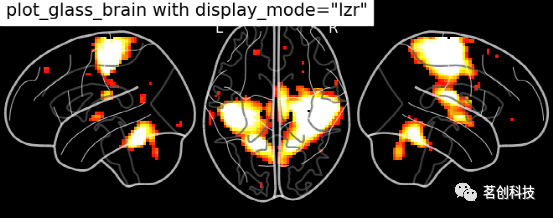

玻璃脑绘制:设置display_mode= 'lzr'。

plot_glass_brain(

stat_img, title='plot_glass_brain with display_mode="lzr"',

black_bg=True, display_mode='lzr', threshold=3

)